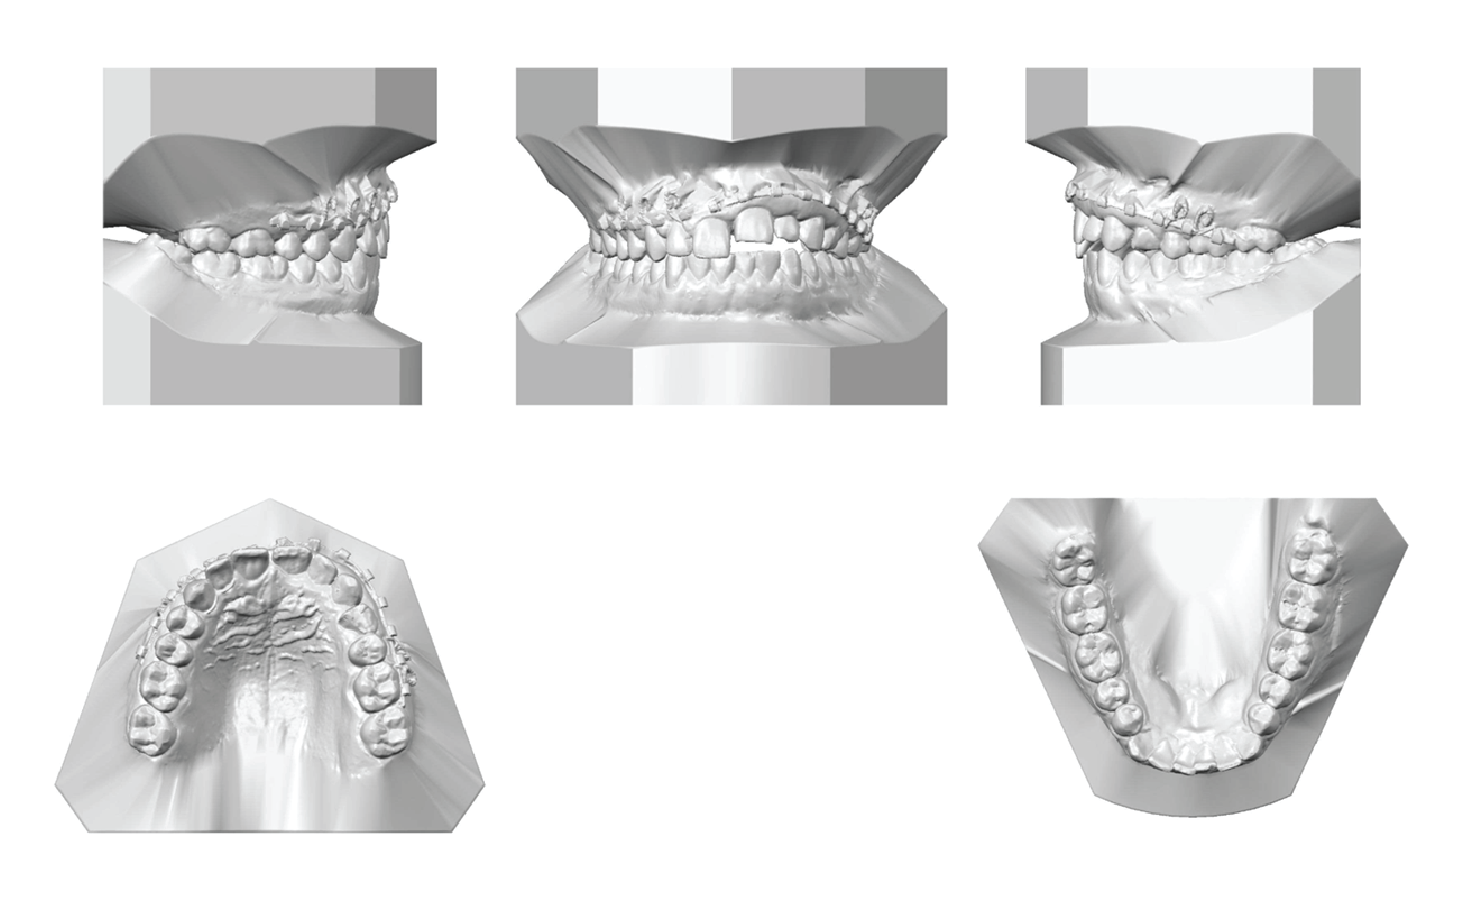

Digital cast analysis (Figure 2) indicated a Class I molar and canine relationship on both the right and left sides. The overjet was between 2 and 4 mm, while the overbite ranged from 2 to -3.2 mm. Both the maxillary and mandibular dental arch widths were within normal limits, with the maxillary inter-canine and inter-molar widths measuring 35.6 mm and 43.5 mm, respectively. The mandibular inter-canine and inter-molar widths were 26.3 mm and 36.1 mm, respectively. Mild crowding was observed in the mandibular arch, with a dental arch space deficiency of 3.3 mm in the mandible. Additionally, a Bolton discrepancy of 0.5 mm was noted due to anterior maxillary teeth excess. Furthermore, marginal ridge discrepancies were present on both maxillary and mandibular arches.

Figure 2: Pre-treatment digital casts. Pre-treatment digital casts show a Class I molar and canine relationship on the right side, a Class I molar relation on the left side, and a Class II canine relation on the left side with an open bite on the maxillary left central, lateral, and canine. Both maxillary and mandibular dental arch widths were mildly constricted, with mild crowding in the mandibular arch. We can also observe marginal ridge discrepancies on both maxillary and mandibular arches, and a Bolton discrepancy due to a maxillary anterior teeth excess.